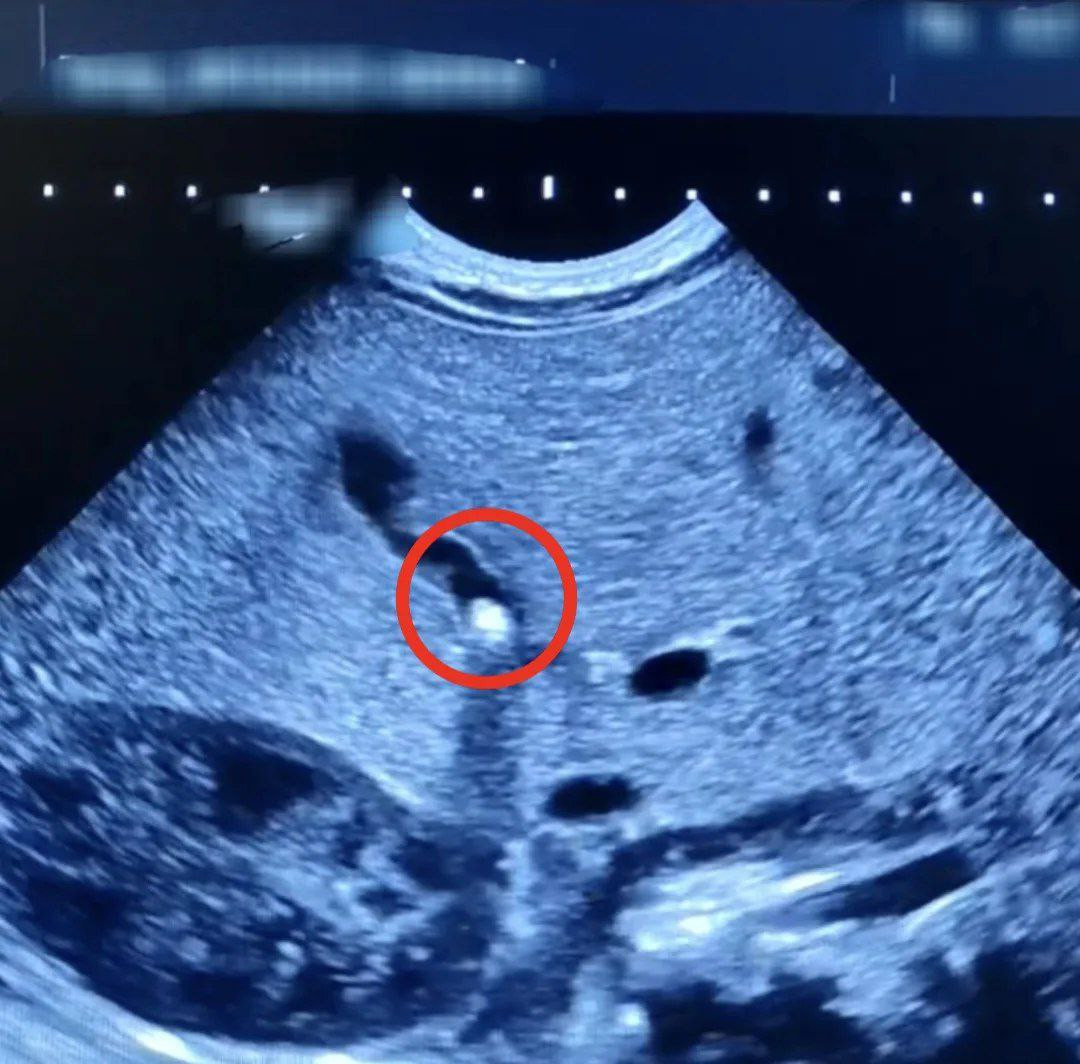

Мать малыша обратилась за медицинской помощью из-за недостаточной прибавки в весе и желтушного оттенка кожи и глаз у ребенка. Ультразвуковое исследование показало наличие небольшого камня, который частично перекрывал желчный проток. Ребенок прошел лечение в стационаре, его состояние улучшилось, восстановился отток желчи, и началась нормальная прибавка массы тела. В настоящее время пациент выписан и находится под наблюдением врачей.